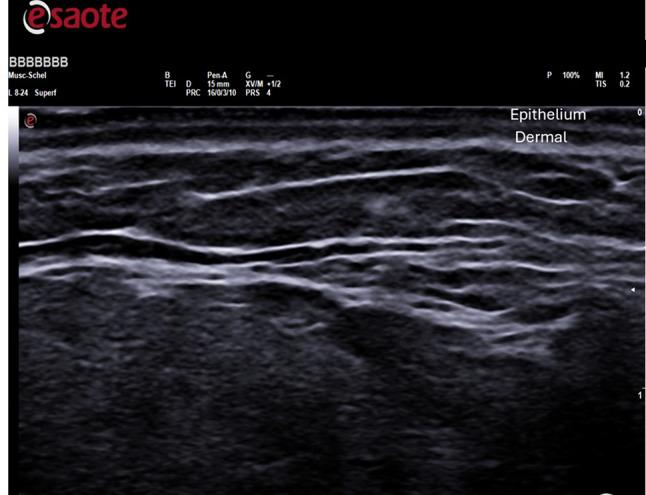

A total of twenty women, with an average age of 45 and ranging from 35 to 64 years old, participated in the study, including 8 in menopause and 12 in the childbearing age group. Mesotherapy was used to administer HAAM to the patients. Prior to and three months after the treatment, each patient underwent small circular punch biopsies. Ultrasound examinations were conducted using B-mode, capturing 2D images in longitudinal or transverse orientations with frequencies ranging from 5 to 13 Mega-hertz (MY LAB X8, ESAOTE, Genova, Italy). A total of 60 ultrasound examinations were taken, with 30 collected before treatment and 30 after treatment.

The histological analysis demonstrates an increase in fibroblast activity resulting in the production of Type III reticular collagen, as well as an increased number of blood vessels and epidermal thickness. However, the analysis of ultrasound data before and after treatment showed no statistical difference in skin thickness in malar area, chin and mandibular angle.